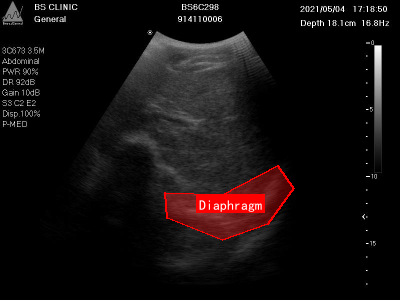

上图展示了另一张膈肌超声影像图,图像中清晰标注了膈肌位置及其周围的解剖结构。通过数据增强技术,我们可以创建更多样化的训练样本,帮助模型更好地学习膈肌在不同条件下的特征表现。

上图展示了模型在测试样本上的检测结果,红色框表示模型预测的膈肌位置,绿色框表示真实标注。从图中可以看出,模型能够准确检测膈肌位置,即使在不同形状和位置的膈肌上也能保持较高的检测精度。

本数据集为Diaphragm数据集v7版本,采用CC BY 4.0许可协议,由qunshankj平台用户提供并导出。数据集包含315张腹部超声检查图像,所有图像均以YOLOv8格式标注,专注于膈肌(Diaphragm)的识别与定位。每张图像均为BS CLINIC机构的临床超声检查结果,设备型号为BS6C298,包含患者编号、检查时间、扫描深度(约16.8-18.1cm)、频率(16.8Hz)等临床参数。左侧参数栏详细记录了探头类型(如3D/7-3.5M、3CD73 SSM等)、检查部位(Abdominal腹部)、功率(PWR 90%)、动态范围(DR 92dB)、增益(Gain 100-108)、滤波设置(LB 0.2/C2 E2、G8 C2 E2等)及显示模式(Disp 100%、P-MED)等技术参数。图像主体呈现典型的腹部横断面超声灰度影像,清晰显示腹腔内不同组织的回声差异,包括低回声区和高回声结构。膈肌在图像中表现为弧形高回声带,通过红色多边形轮廓线精确标注,明确标识这一区分胸腔与腹腔的重要解剖结构。右侧刻度标尺用于测量深度,整体图像质量良好,细节可辨,为临床诊断提供膈肌位置、形态及周围组织关系的可靠参考。数据集未应用任何图像增强技术,保持了原始临床数据的真实性,适用于膈肌超声影像的自动检测算法研究与模型训练。